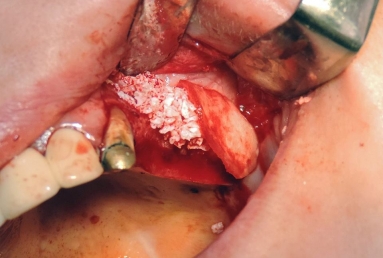

Final situation: an external sinus lifting procedure was performed. The sinus membrane was lifted off the sinus walls and new bone was applied in the vertical space created ( Bio Oss- switzerland- bovine origin). After 6 months, while the new bone is integrated in the maxillary bone of the patient, dental implants can be applied. the case is still during treatment.